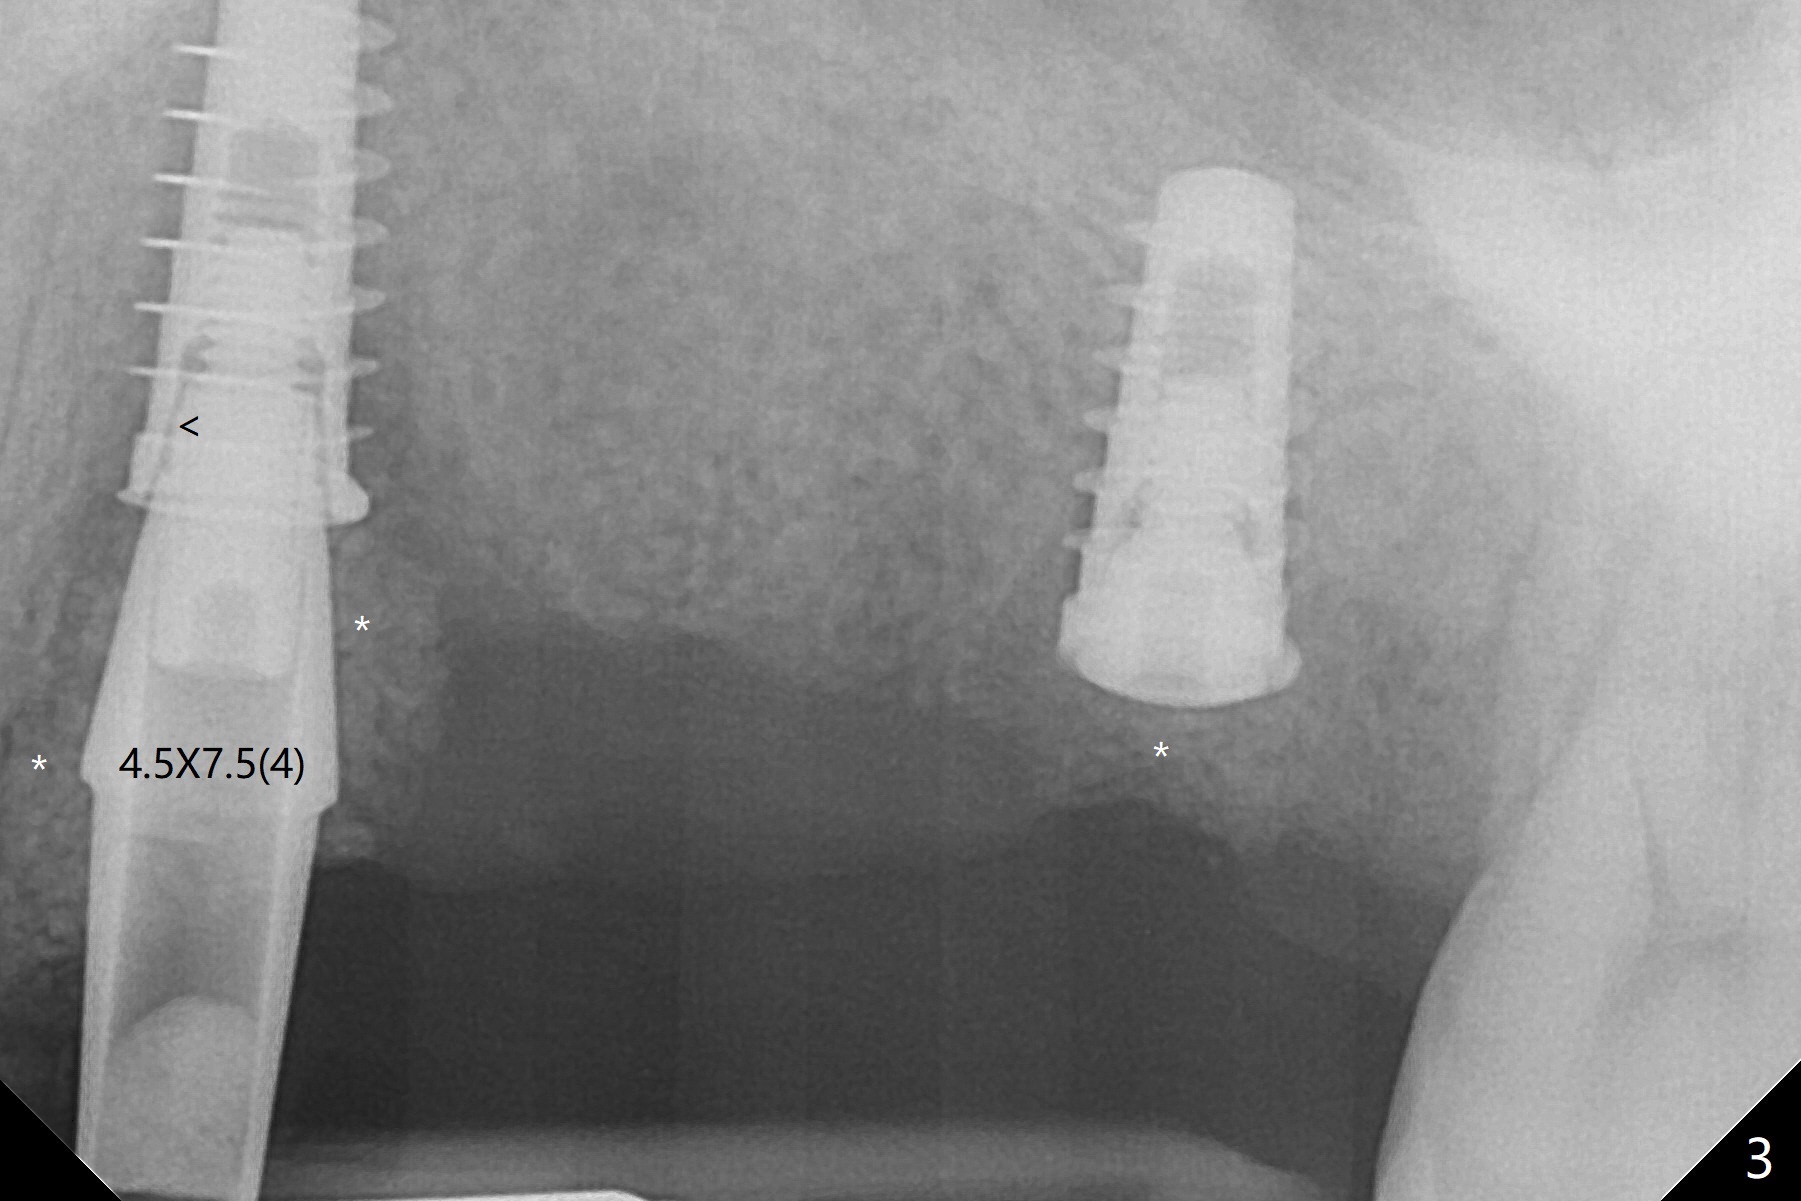

Immediate placement at #12 is smooth with 20 Ncm, whereas delayed one at #14 involves sinus membrane perforation; after insertion of PRF and mixture of autogenous bone and allograft, a shorter dummy implant tries in with stability (Fig.1). The final implant at #14 has ~60 Ncm, but the coronal palatal bone may be insuficient (Fig.2). Sticky bone is placed to bury the implant at #14 (Fig.3 *). After placement (incomplete, Fig.3 <) of a 4.5x7.5(4) mm pair abutment, setting acrylic is applied around the abutment, over the bone graft at #14 (to prevent loss) and pressed into the undercuts of the proximal surfaces of the neighboring teeth for retention (Fig.4). The sockets at #12 heals 8 days postop when a 2nd acrylic dressing dislodges (Fig.5). It appears that the retention of 3-unit acrylic dressing is poor. The wound at #14 also heals, but it would be better to make an incision to save the soft tissue (Fig.6). The bone/implant gap reduces at #13 five months postop (Fig.7 (complete abutment seating)). There is no implant thread exposure at #13 (immediate), while minor exposure mesial to #15 (delayed). The patient complains of food impaction between #13 and 14 buccally 6 months post cementation (Fig.8). Return to Upper Molar Immediate Implant, No Deviation 19 Next Case Xin Wei, DDS, PhD, MS 1st edition 01/21/2020, last revision 02/03/2021